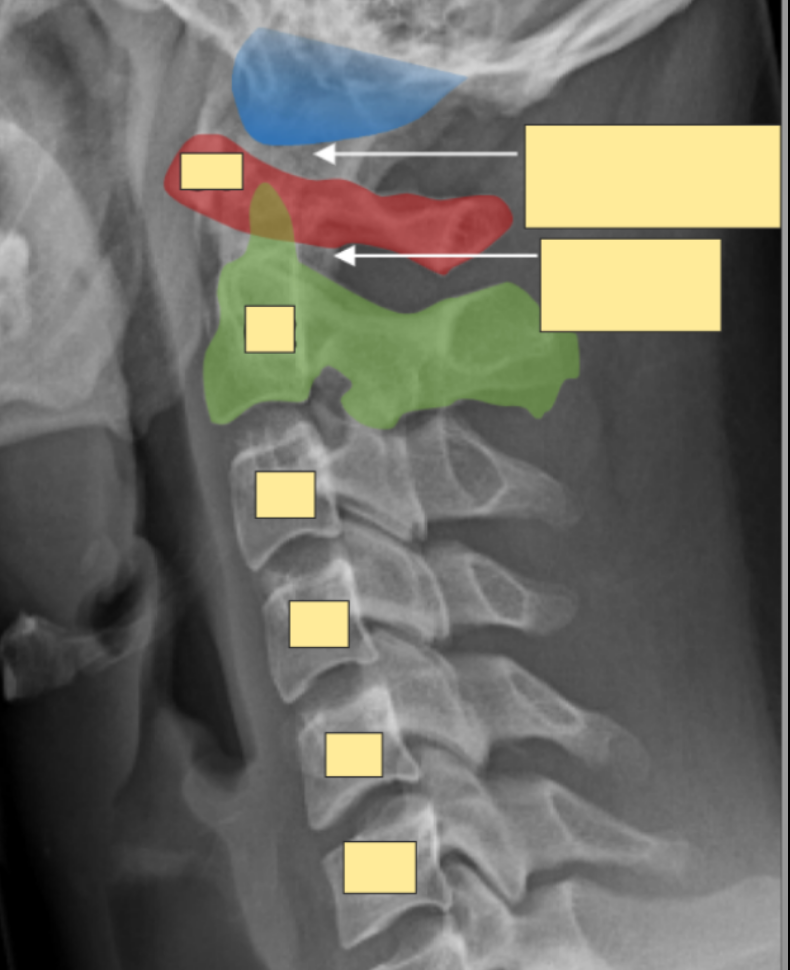

Which are the atypical cervical vertebrae?

atlas (C1) and axis (C2), C7

What are the features of atlas? (c1)

1) Superior articular facet (articulates with occipital condyles forming altanto-occipital joint)

2) No body - posterior arch instead

3) Allows you to say yes - allowing for flexion and extension

4) No spinous process

10

What are the features of axis? (c2)

1) Dens (body of atlas) - articulates with the vertebral odontoid process atlantoaxial joint

2) Superior articular facet (where the atlas sits)

3) Allows you to say no

11

What is the function of the dens?

dens acts as pivot allowing atlas and the occipital bone above for the head to rotate on axis side to side

NO ZYGOPOPHASYEAL JOINT BWTWEEN C1 AND 2